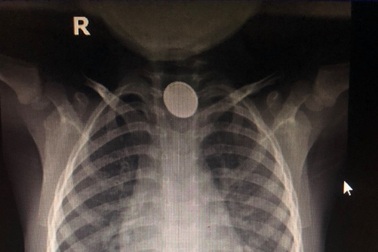

Bé trai bị hóa chất ăn mòn thực quản vì nuốt cục pinBác sĩ phát hiện trong thực quản bệnh nhi có dị vật bị kẹt ngang nên tiến hành nội soi gắp ra. Dị vật là cục pin có nhiều hóa chất độc hại đã ăn mòn thực quản khiến bé bị tổn thương nặng.